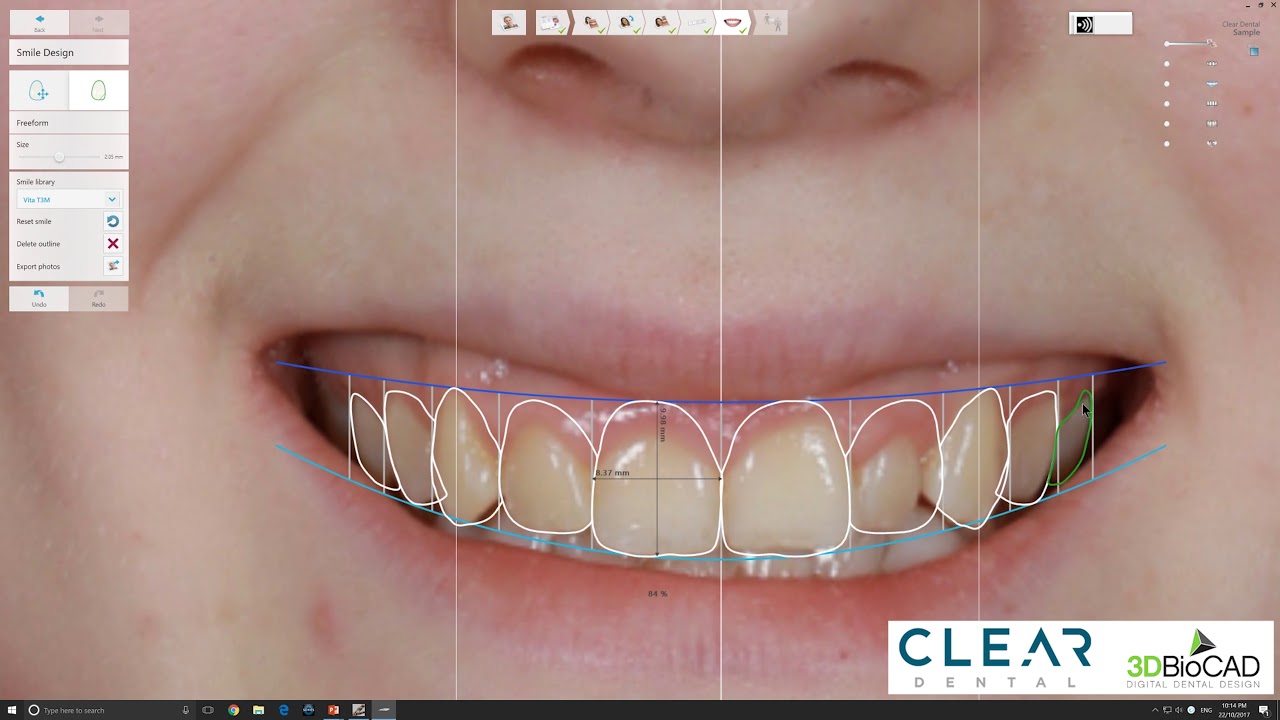

3shape Smile Design

Immerse yourself in the artistic beauty of 3shape Smile Design through substantial collections of inspiring images. blending traditional techniques with contemporary artistic interpretation. transforming ordinary subjects into extraordinary visual experiences. The 3shape Smile Design collection maintains consistent quality standards across all images. Ideal for artistic projects, creative designs, digital art, and innovative visual expressions All 3shape Smile Design images are available in high resolution with professional-grade quality, optimized for both digital and print applications, and include comprehensive metadata for easy organization and usage. Our 3shape Smile Design collection inspires creativity through unique compositions and artistic perspectives. Instant download capabilities enable immediate access to chosen 3shape Smile Design images. Our 3shape Smile Design database continuously expands with fresh, relevant content from skilled photographers. The 3shape Smile Design collection represents years of careful curation and professional standards. Diverse style options within the 3shape Smile Design collection suit various aesthetic preferences. Multiple resolution options ensure optimal performance across different platforms and applications. Professional licensing options accommodate both commercial and educational usage requirements. Each image in our 3shape Smile Design gallery undergoes rigorous quality assessment before inclusion. Time-saving browsing features help users locate ideal 3shape Smile Design images quickly. Advanced search capabilities make finding the perfect 3shape Smile Design image effortless and efficient.